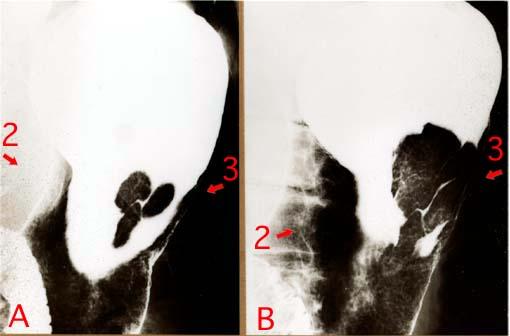

clasificación del pacienteTumor Maligno del Sistema Linfático/Linfoma Maligno

parte(separada por órganos)estómago(región)/cuerpo

método de exámenRayos X

clasificación ectoscópica de tumoresTipo 1(Tipo protuído)/

diámetro mayor del tumor40 -

grado de penetraciónmp